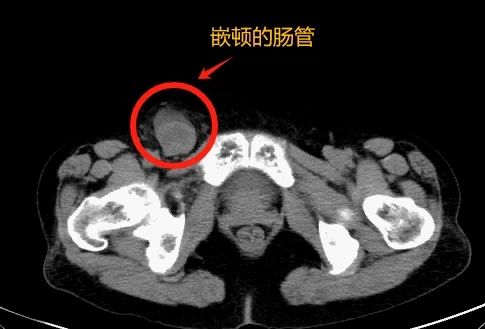

嵌顿疝是疝气严重发展后的一种情况,危害很大。当腹腔器官疝进入时,不能自行复位,卡在疝囊中时,会形成嵌顿疝。这不仅会使患者遭受疼痛和破坏,如果不及时治疗,还会造成肠梗阻、器官坏死等严重后果,对患者的健康甚至人身安全构成极大威胁。

我院普外科副主任刘宗航立即对她进行了腹腔镜单侧腹股沟疝修复。在手术过程中,我们可以看到王奶奶嵌顿疝的内容是小肠,嵌顿肠管有局部淤血,没有明显的小肠坏死,只有小肠浆膜表面有裂纹。外科医生为她修复了小肠浆膜,松开疝环后小肠血运恢复。

随后,普外科副主任刘宗航为她进行了腹腔镜下单侧股疝修补术,在术中确定右侧股疝嵌顿,并将小肠嵌入其中。

可惜局部肠道变黑,观察后肠道颜色无法恢复,说明肠道缺血坏死已经发生,然后医生切除并吻合了坏死的部分小肠。